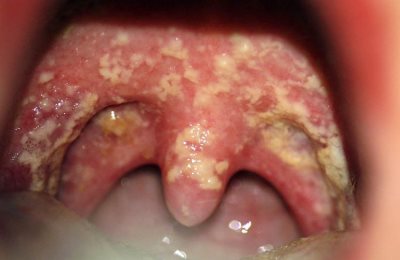

Их научное название – казеозные пробки. Другими словами – это шарики, в которых содержится гной, патогенные микроорганизмы, частицы пищи, отмершие ткани. Они вызывают воспаление в миндалинах.

На что последние реагируют увеличением и отеком. Избавиться от комочков самостоятельно, особенно если они на задней стенке глотки, невозможно.

Ангина или острый тонзиллит – опасная патология, её возбудители вызывают массу осложнений и поражают сердце, легкие, почки. Гнойные комочки покрывают миндалины и заднюю стенку глотки.Болезнь протекает очень тяжело.

Хронический тонзиллит – это заболевание, при котором в миндалинах постоянно живет инфекция. Именно поэтому они всегда увеличены, а их обладатели склонны к частым болезням. Гнойные пробки в горле являются источником неприятного запаха изо рта.

Температура при хронической ангине ниже, но может держаться неделями. На миндалинах и задней стенке глотки периодически появляются белые комочки. К сожалению, многие люди пытаются самостоятельно избавиться от казеозных пробок.

Пробки с гноем в горле, или тонзиллярные пробки, часто возникают при хроническом тонзиллите, фарингите и других заболеваниях, связанных с воспалением миндалин. Люди описывают это состояние как неприятное, сопровождающееся болью, неприятным запахом изо рта и затруднением глотания. Важно понимать, что такие пробки образуются из-за накопления бактерий, остатков пищи и клеток, что приводит к образованию гнойных масс.